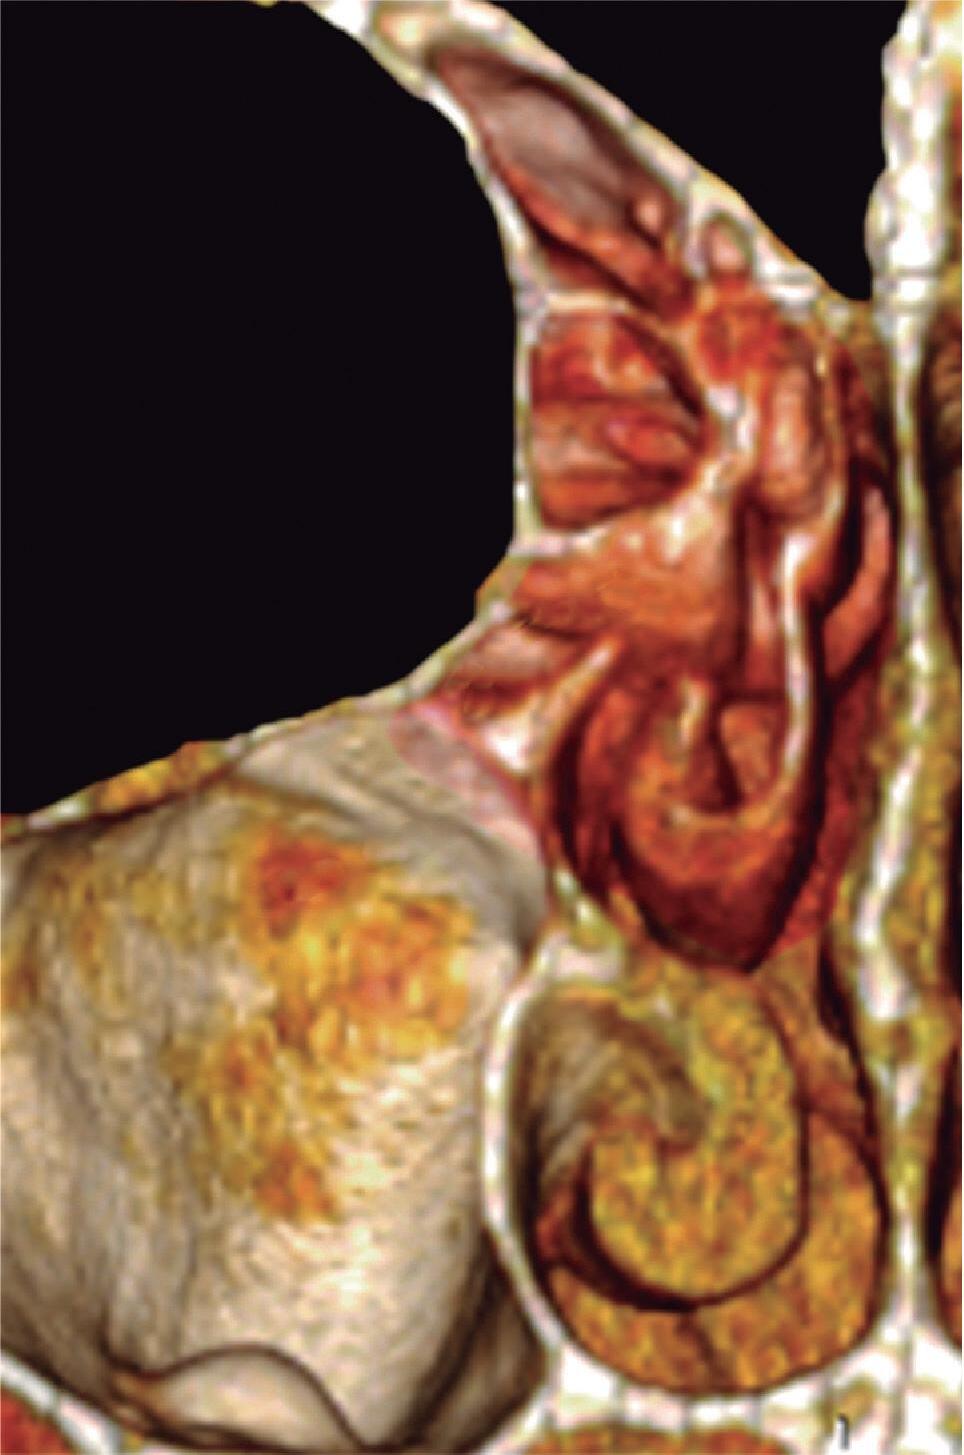

1-4. TC e reconstrução 3D com destaque para estrutura etmoidal (em vermelho), funcionando como câmaras de baixa pressão para drenagem do seio maxilar.

1-7. TC com reconstrução 3D mostrando em vermelho apenas o seio etmoidal e não o osso etmoidal, e sua relação com a fossa nasal, o seio maxilar, órbita e fossa anterior.